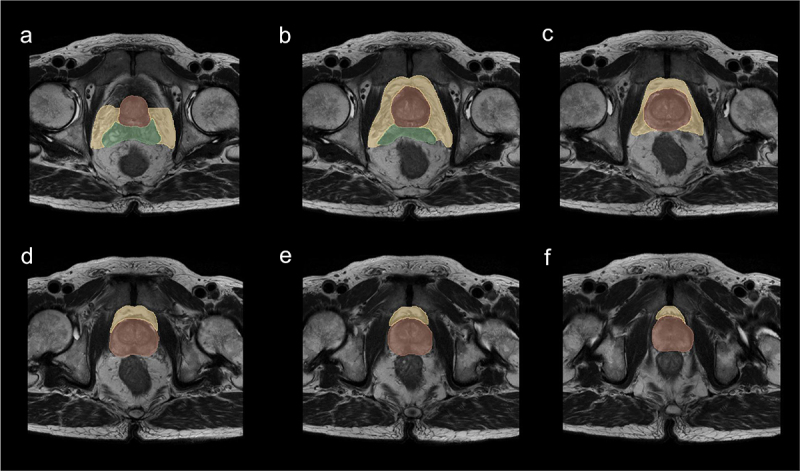

Methods: A retrospective study of 151 PCa patients (October 2010-November 2022) was conducted. Radiomic features were extracted from axial T2-weighted MRI of PPAT, and normalized PPAT was calculated as the ratio of PPAT volume to prostate volume. A radiomics score (Radscore) was developed using logistic regression with 16 features selected via LASSO regression. Independent predictors identified through univariate and multivariate logistic regression were used to construct a nomogram. Predictive performance was assessed using ROC curves, and internal validation involved 1000 bootstrapped iterations.

Abstract Image